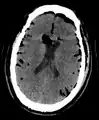

Additional images

Large pneumocephaly secondary to surgical wound